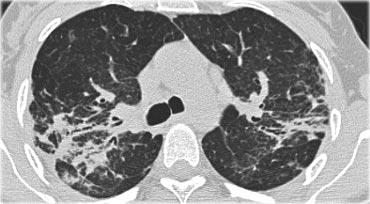

Dưới đây là hai ví dụ về viêm phổi quá mẫn bán cấp.

Có thể thấy các nốt trung tâm tiểu thùy bờ không rõ dạng kính mờ.

Đây là một trường hợp khác của viêm phổi quá mẫn bán cấp.

Có thể thấy hình mờ mờ nhạt ở trung tâm các tiểu thùy thứ cấp (mũi tên) với vùng dưới màng phổi được bảo tồn.

Hình ảnh HRCT này cũng cho thấy hình mờ trung tâm tiểu thùy mờ nhạt ở bệnh nhân HP bán cấp.

Lưu ý ranh giới không rõ của các nốt trung tâm tiểu thùy này.

Đôi khi các hình mờ trung tâm tiểu thùy có hình thái dạng nốt rõ hơn như trong trường hợp này.